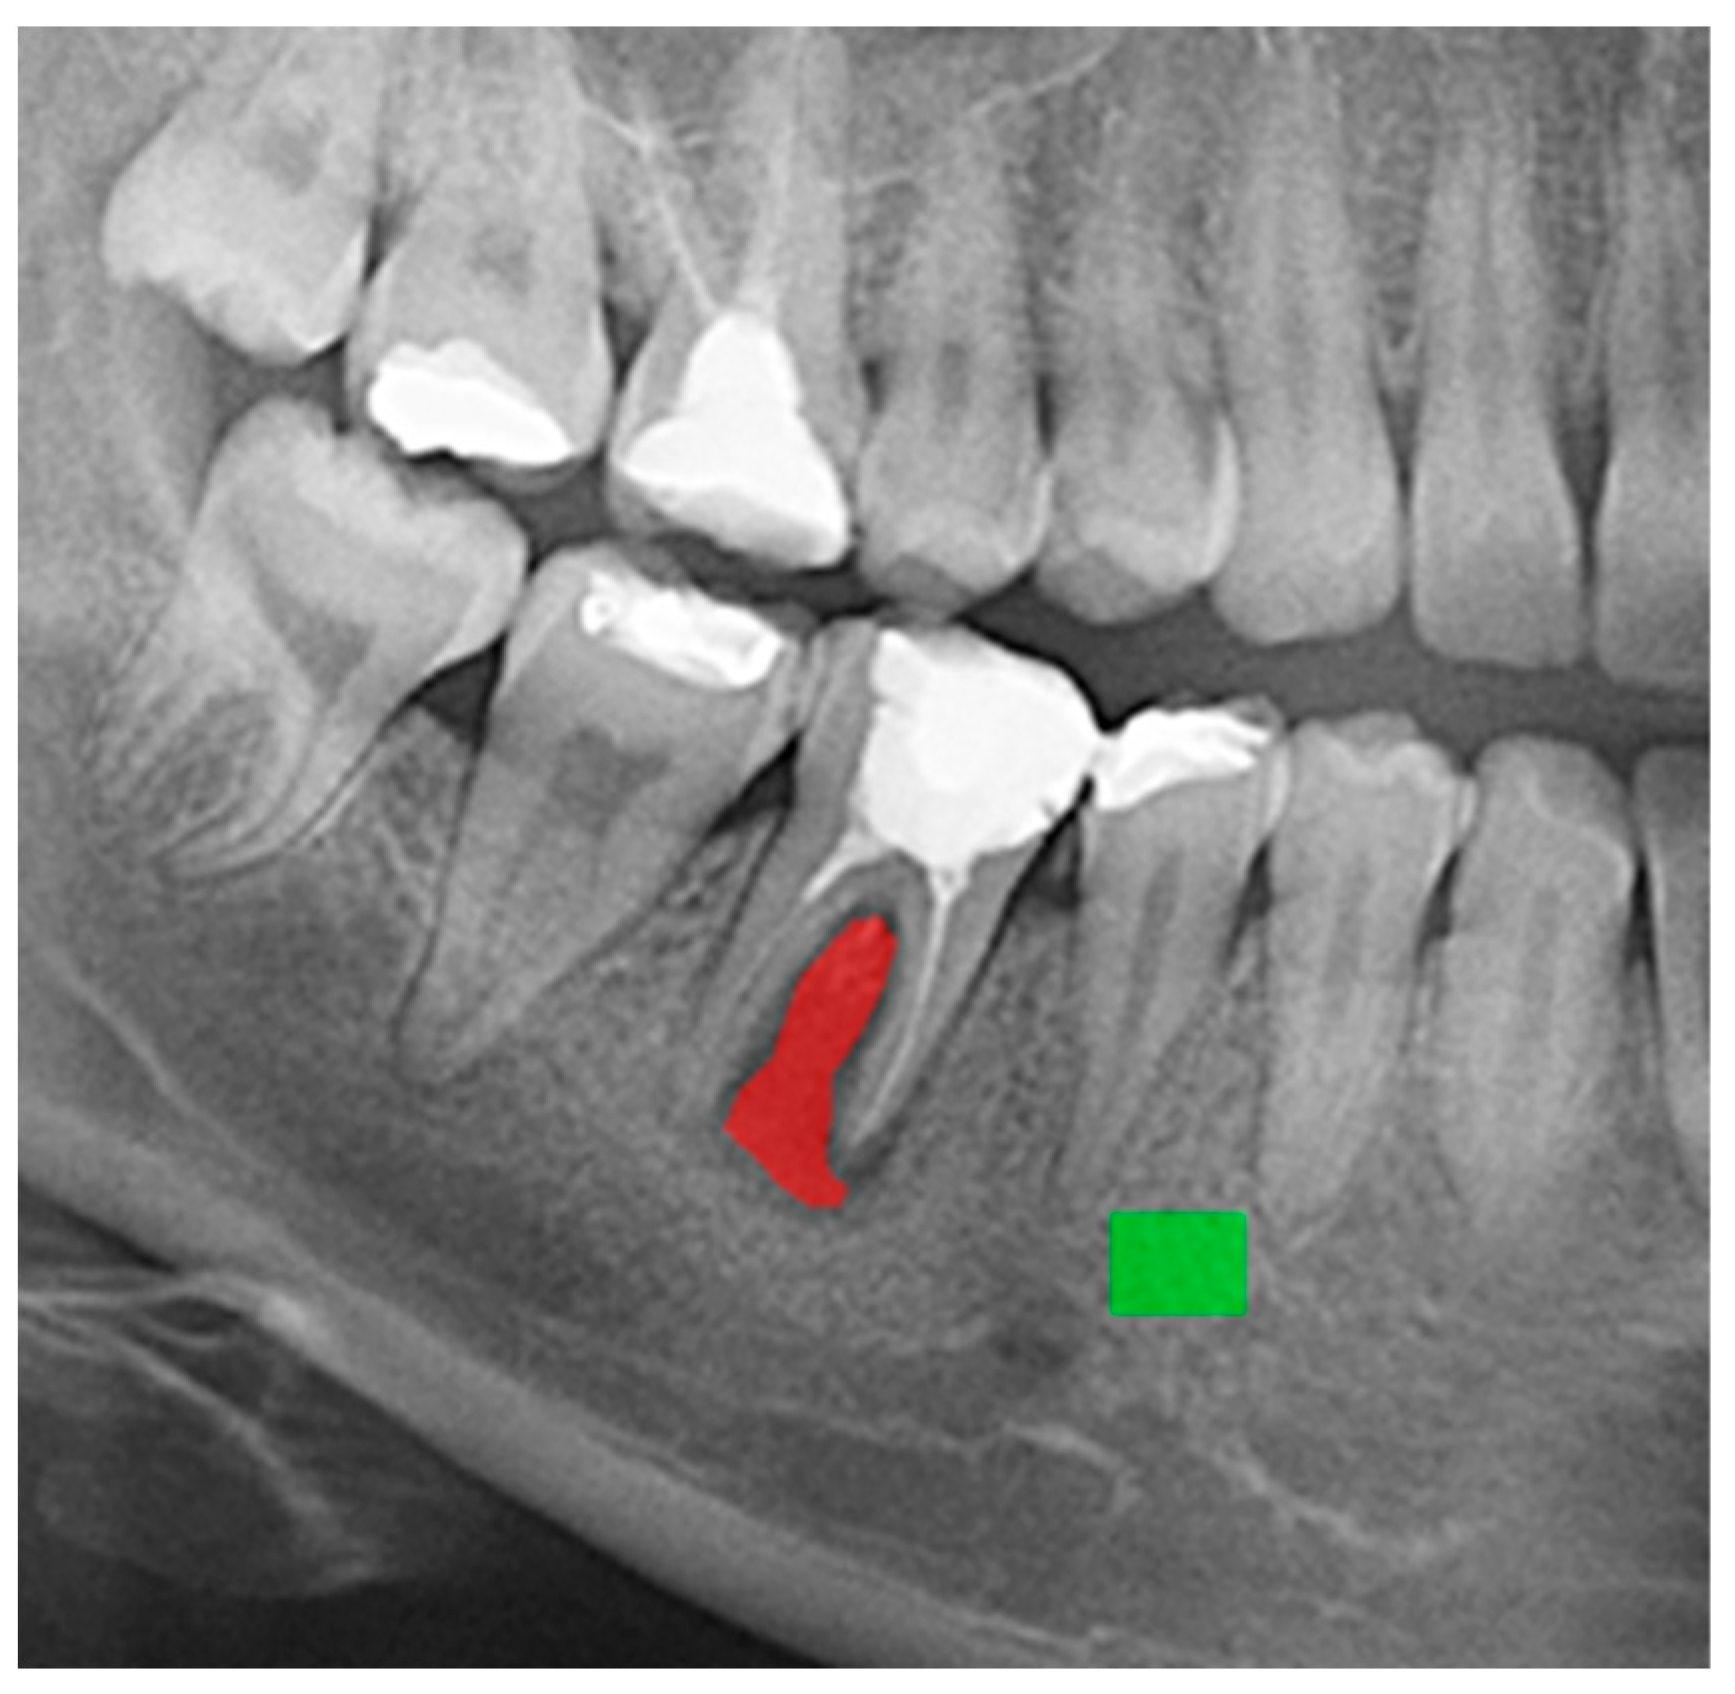

2.2.1. Mask Annotation